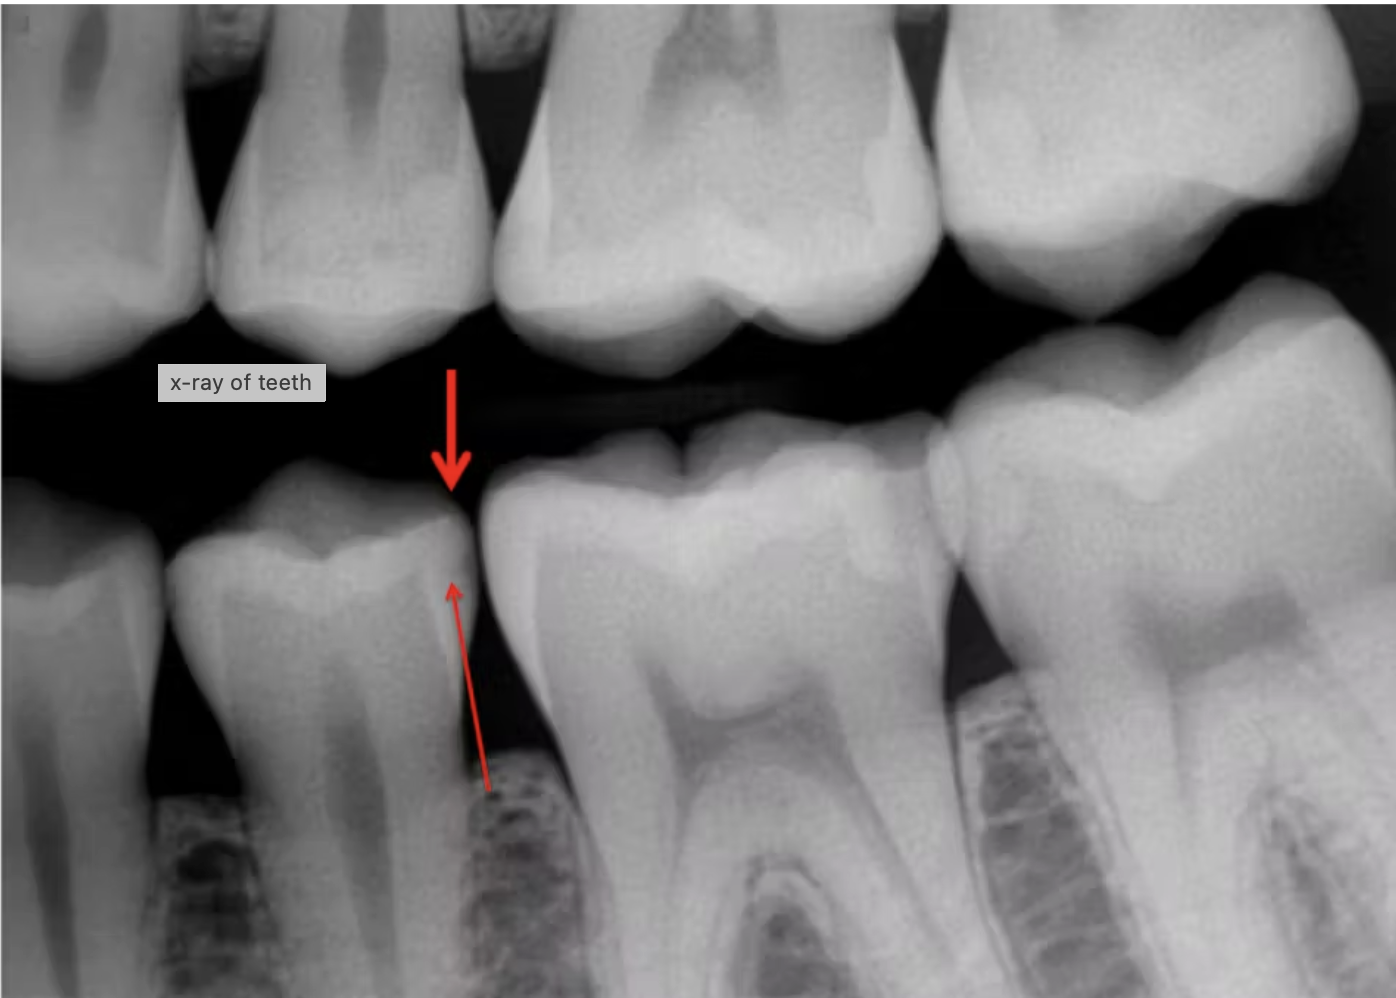

Hình 1:

Tổn thương sâu răng trên lâm sàng thường lớn hơn hình ảnh thể hiện trước khi phục hồi, nhưng việc phục hồi các tổn thương nhỏ như thế này là lý tưởng. Nghiên cứu cho thấy các miếng trám nhỏ có tuổi thọ dài hơn đáng kể so với các miếng trám lớn, giúp tiết kiệm thời gian điều trị, bảo tồn độ bền của răng và kéo dài tuổi thọ phục hồi.